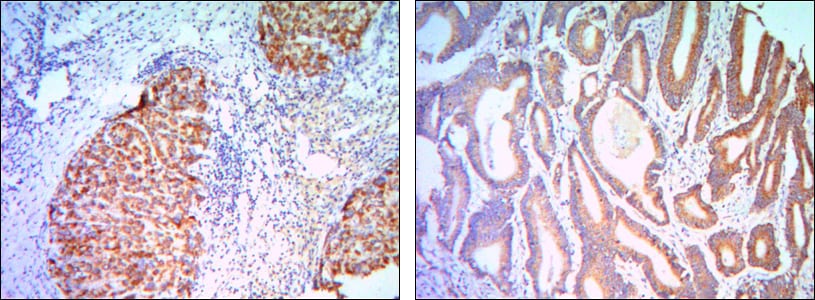

分类: 科研抗体货号: 30085别名: PFE; PTHR; PTHR1; MGC138426; MGC138452; PTH1R应用: IHC,IF反应种属: Human,Mouse